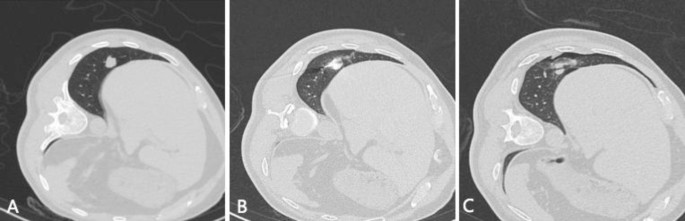

Standard-dose protocol CT-guided microwave ablation of lung tumor. A 73-year-old male patient, with a height of 1.69 m, weight of 73 kg, and a BMI of 25.56. He had a solitary lung adenocarcinoma in the lower lobe of the right lung. He cannot endure surgy because of renal failure, and received standard-dose protocol CT-guided lung tumor MWA. The local scan radiation dose was 0.812 mSv, and the overall radiation dose during ablation was 9.53 mSv for this patient. A: Preoperative local lesion scan clearly shows the solid nodule. B During the puncture process, the ablation needle punctures to a satisfactory ablation site. C: Whole lung scan images after ablation show that the lesion was completely covered by a ground glass halo.